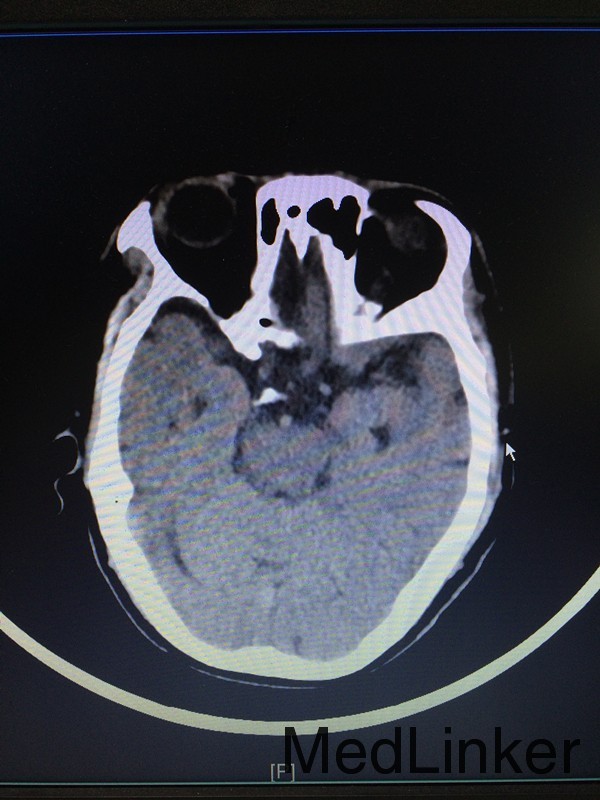

主诉:左侧肢体乏力28天 病史:患者60岁男性,于入院前28天无明显诱因出现左侧肢体乏力,伴言语不清,表现为行走不稳、神志模糊,较烦躁,无头痛、头晕、恶心呕吐等,于当地医院行头颅CT提示:大脑中动脉高密度影。患者第二天出现头痛伴呕吐,急查头颅CT提示:大面积脑梗。

查体:左侧上肢2级,下肢2级,右侧肢体肌力正常 辅助检查:查头颅CTA提示:右侧额叶及岛叶(包括基底节)脑梗塞,轻度脑萎缩,CTA未见明显异常

诊断:右侧额叶及岛叶大面积脑梗塞 治疗:予活血化瘀、改善血管痉挛、脱水降颅压等治疗,并申请康复、高压氧等治疗。

随访:患者病情缓解出院 讨论:患者60岁男性,突发大面积脑梗塞,可能是由脑动脉主干阻塞所致,CT呈现大片状低密度阴影,多为脑叶或跨脑叶分布,脑组织损害范围较大,临床上除表现脑梗塞的一般症状外,还伴有意识障碍及颅内压增高。不排除为体循环的血栓掉落至大脑动脉引起。